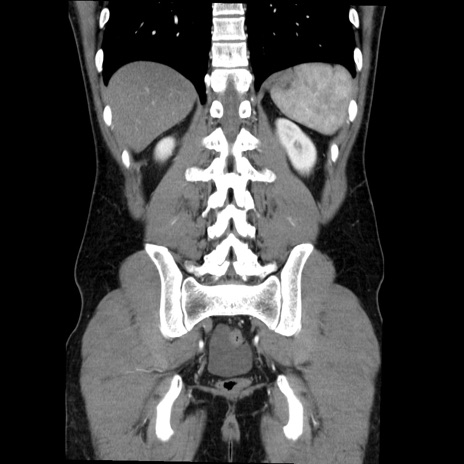

症例36(冠状断像)

【症例】20歳代 男性

【主訴】心窩部痛

【現病歴】今朝より上腹部痛あり。一旦軽快していたが再度出現したため救急要請。昨日夕に白身の魚を含む刺身を食べた。

【身体所見】BP 136/89mmHg、HR 74/min、BT 37.0℃、腹部:膨満、軟、心窩部に圧痛あり。反跳痛なし、筋性防御なし、腸雑音やや亢進あり。

【データ】WBC 17700、CRP 0.48